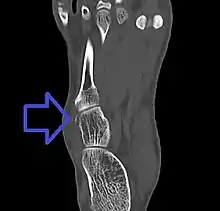

Avulsion fracture of the cuboid on CT

A cuboid fracture is a fracture of the cuboid bone of the foot. Diagnosis is by X-ray imaging, magnetic resonance imaging, or bone scan.[1] Treatment may be conservative or involve surgery, depending on the type of fracture.[1] They are rare.[1]